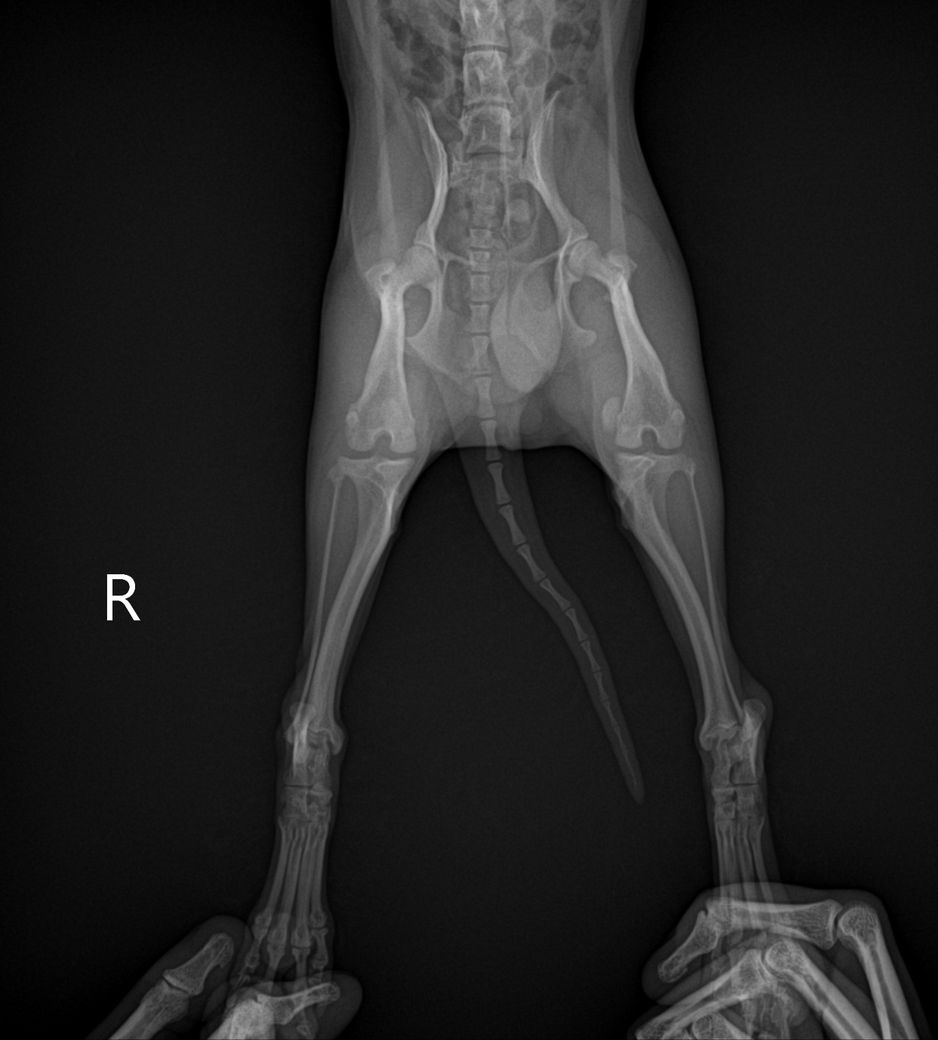

담당 의사선생님께서 십자인대의 문제는 확인이 어렵다고 하셨는데, 보통 X-ray로 확인하지 않나요..?ㅠㅠ 그래서 아하에 계시는 수의사 분들께 병원에서 받아온 X-ray 사진과 병원에 진료 후 내려놨을 때 걷는 영상을 첨부하오니, 100%가아니더라도 십자 인대 수술이 필요해보이는지, 다른 소견은 없는지 등의 진단을 부탁드립니다..!ㅠㅠ

30cm가 이니라 10여도 터질 십자인대는 터집니다. 다만 첨부한 사진에서 양쪽 뒷다리의 측면 사진이 모두 첨부되어야 관절낭을 중심으로 비교 평가할 수 있는데 사진이 누락되어 판단할 수 없습니다. 다만 주관적으로 2번째 첨부 사진에서 아킬레스건의 부종 양상이 관찰되고 슬개골 관절낭의 심한 종창은 보이지 않아 십자인대 단열보다는 아킬레스건 부분단열을 먼저 고려해야 할것으로 보입니다. 주치의의 지시에 따라 평가 진행해도 크게 무방합니다.